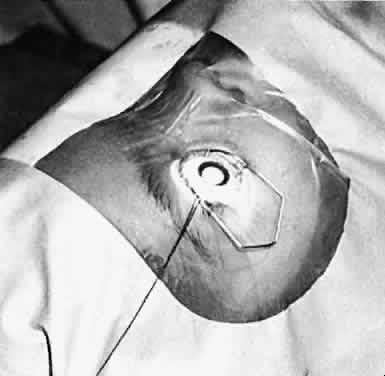

Bilateral Complete Cataracts

If the lens opacity is complete and involves both eyes, the cataract should be removed in the eye with the most complete lens opacity. The fellow eye should be treated as soon as the first eye recovers from surgery. This interval should be brief (5 to 10 days) in very young children. If a health problem precludes repeated anesthetic sessions, consideration may be given to performing the surgery on both eyes during the same anesthetic session, with the use of different instrumentation and separate operative fields.4,5

Health of the Child

An assessment of the general health of a child is important when considering cataract surgery because general anesthesia is required for the operation. Premature infants with severe bronchopul-monary dysplasia may have unacceptable risksassociated with the use of general anesthesia. Other children who have systemic diseases such as galactosemia, homocystinuria, congenital heart disease, and Marfan's syndrome or who have experienced trauma have additional risks associated with general anesthesia. For these children, appropriate consultation is needed to assess the risks of the procedure before proceeding with surgery.